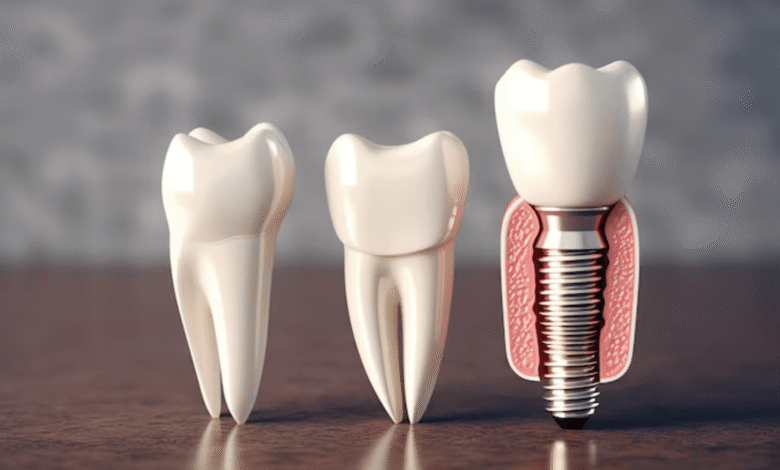

ایمپلنت دندان بهعنوان بهترین روش جایگزینی دندان شناخته میشود. دلیل آن کاملاً مشخص است؛ طبیعیترین ظاهر، بیشترین استحکام و طول عمر بالا. اما یکی از رایجترین پرسشها بین بیماران این است که چرا قیمت ایمپلنت دندان در کلینیکهای مختلف متفاوت است؟

چرا ایمپلنت دندان بهترین روش جایگزینی محسوب میشود؟

در سالهای گذشته، روشهایی مانند بریج یا دندان مصنوعی طرفداران زیادی داشتند، اما با پیشرفت تکنولوژی و افزایش آگاهی بیماران، ایمپلنت دندان تبدیل به اولین و بهترین گزینه جایگزین شده است.

دلایل این برتری عبارتاند از:

-

جلوگیری از تحلیل استخوان فک

-

عدم آسیب به دندانهای سالم مجاور

استحکام بالا و عملکرد مشابه دندان طبیعی

طول عمر بسیار بالا در صورت مراقبت صحیح

زیبایی و یکپارچگی با لبخند

به همین دلیل، افراد با هر سن و شرایطی تمایل دارند از ایمپلنت دندان استفاده کنند، اما باید بدانیم قیمت ایمپلنت دندان بسته به نوع برند، مواد سازنده و خدمات جانبی متفاوت است.